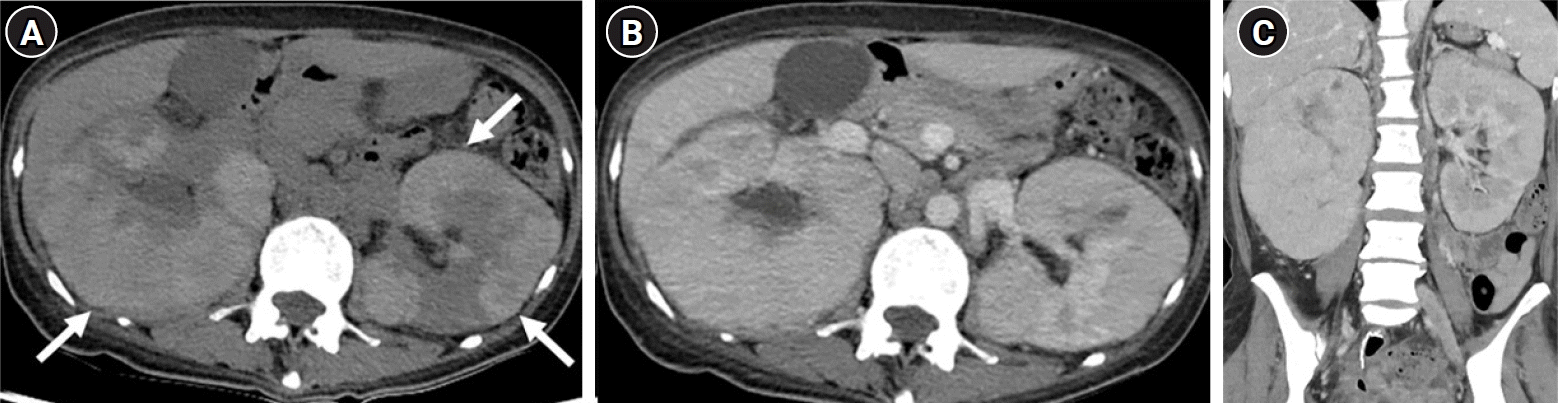

Fig. 6.

Axial unenhanced computed tomography (CT) image (A) and axial contrast-enhanced CT images during the corticomedullary phase (B) and late excretory phase (C), obtained as 3-month follow-up imaging, show a reduction in the size of both kidneys with no significant change in right hydronephrosis. Axial (A) and coronal (D) corticomedullary phase scans reveal multiple nodular or wedge-shaped low attenuation lesions (arrows) with perirenal fat stranding, resembling pyelonephritis.